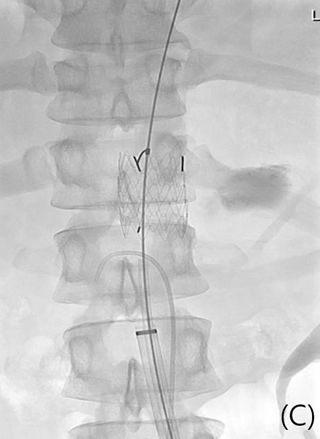

(B,C) Aortic stent-graft (GORE EXCLUDER 23mm/3.3cm) was deployed to cover ruptured pseudoaneurysm with left common femoral approach using 16 Fr sheath and preclose manner.

Fig 3C